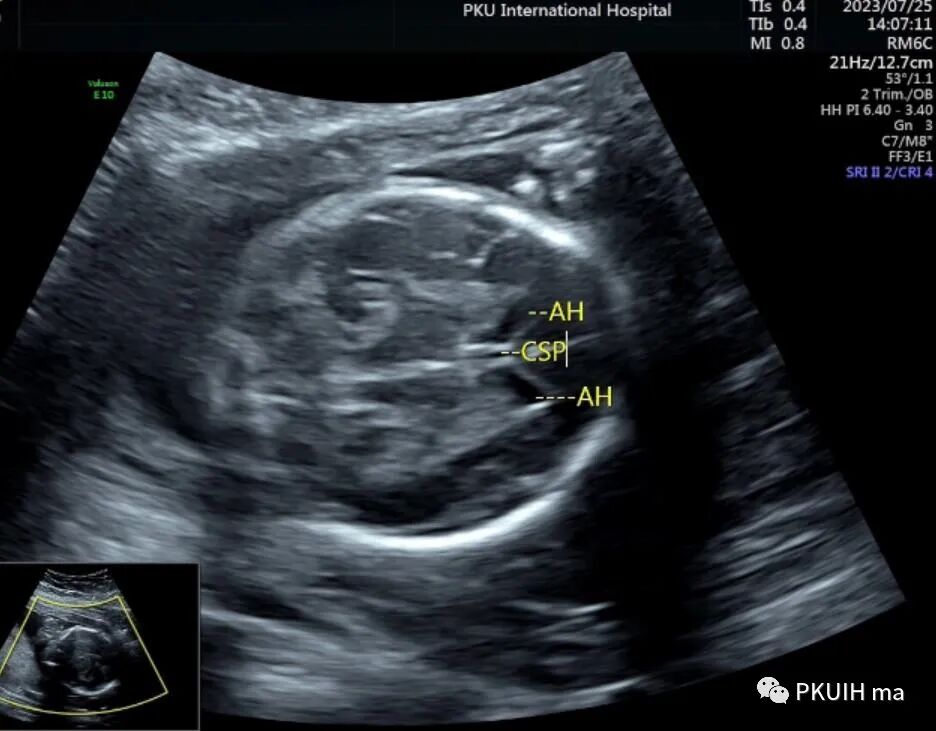

侧脑室看着也还可以没有发现有明显泪滴状,透明隔腔下方穹窿也存在,于是想着先看下胎儿胼胝体

透明隔腔是胎儿中枢神经系统正常发育的一个重要结构。其缺失或形态异常与许多中枢神经系统畸形有关。正常透明隔腔为位于脑中线前部两透明隔间的液体腔,其上方为胼胝体,下方为穹隆,侧壁为透明隔小叶。透明隔腔发育与胼胝体、前联合、穹隆柱密切相关。透明隔腔向后延伸至室间孔,室间孔后方为韦氏腔。